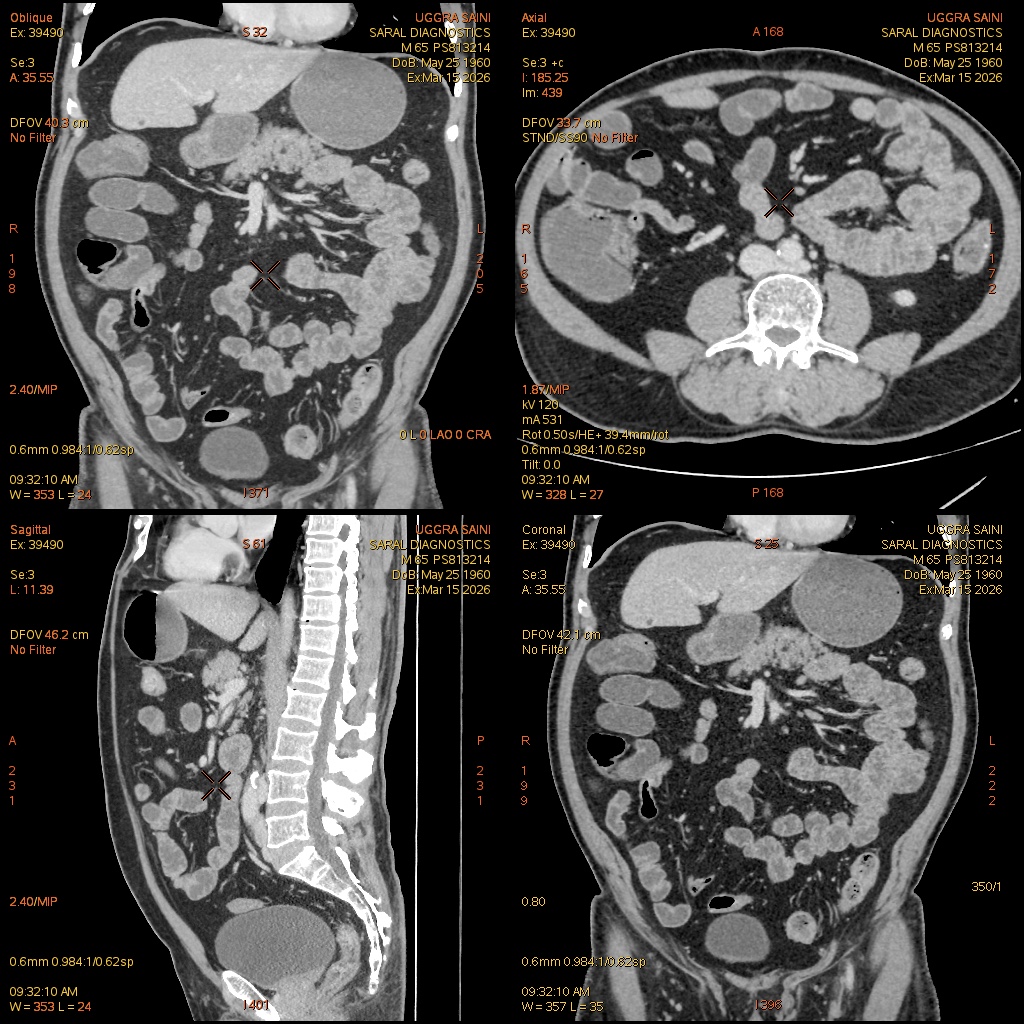

Reference Image

Enterography with IV contrast